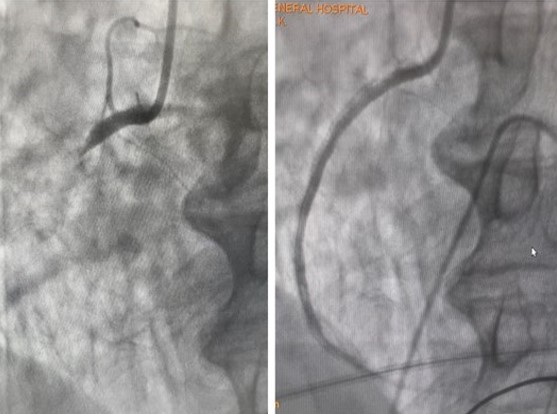

心導管檢查發現(左)冠狀動脈完全阻塞,(右)治療後放置心臟支架箭頭處為二支支架(如下圖)